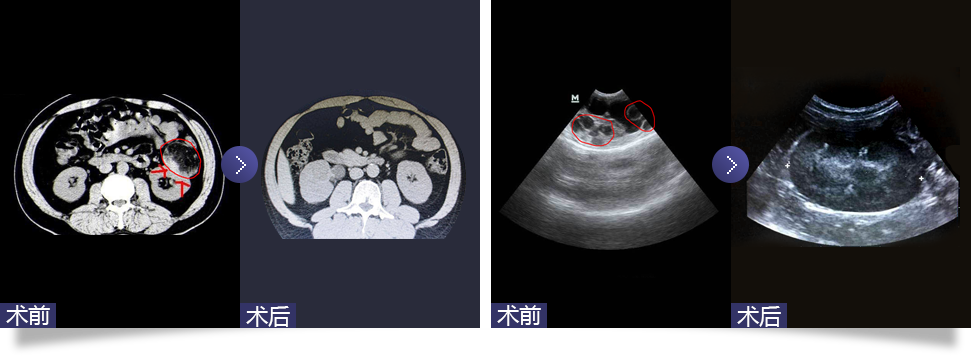

腹腔镜下肾囊肿去顶减压术

Laparoscopic renal cyst deparization and decompression

随着腹腔镜技术在泌尿外科领域的广泛应用,腹腔镜下囊肿去顶减压术成为治疗肾囊肿的主要方法。通过腹腔镜下用超声刀切开腹膜,伤口为1.5-2.0cm,分离肾周脂肪,找到充分暴露的肾囊肿壁边缘,切开囊肿壁并吸净囊液。